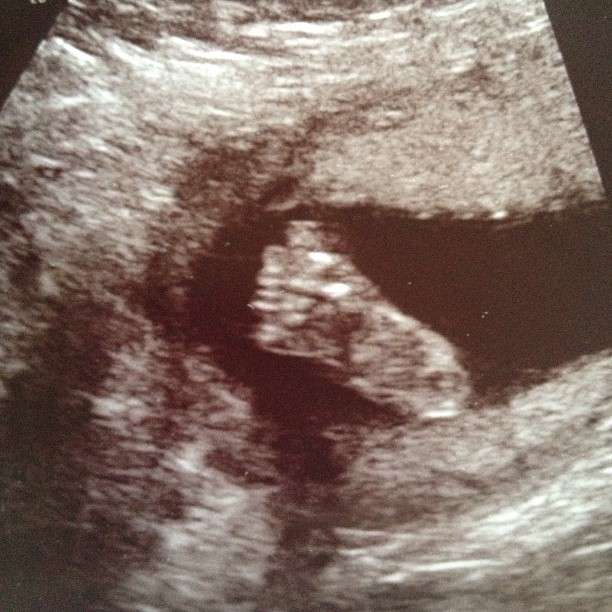

| Little Levi’s foot |

Yes, he will have surgery once he’s born to remove the cysts, and yes he still has a clubbed foot, and yes he might have some brain damage. But I will be able to hold my son in my arms. I will be able to kiss his little heart-shaped mouth and I will be able to tell him face to face that I love him.

Oh my goodness, what a cute little foot!

Love his little foot!!! Prayers still coming for you and your family!